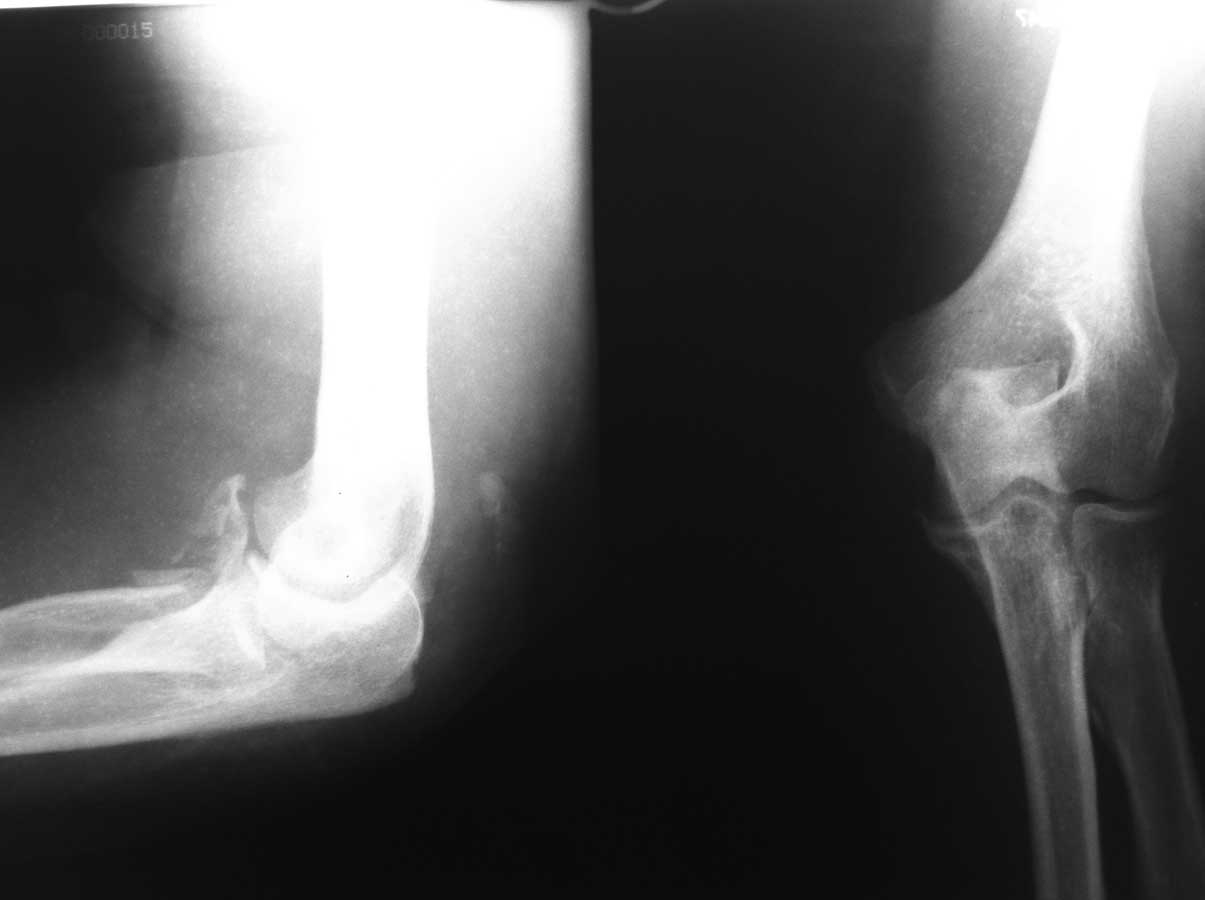

добиться? На представленных снимках нет признаков нарушение конгруэнтности

суставных поверхностей. Сделайте снимок в строго боковой проекции. Больше

> Пациентка 66 лет. Травма в результате падения на руку 12.04.2012. при

> обращении в п-ку

> выполнены Р-гр.

> 21.05.2012 выполнены контрольные Р-гр и больная направлена на

> госпитализацию. Местно:

> Отека нет, сосудистых и неврологических расстройств в конечности нет.

> движения в локтевом

> суставе 10-15 гр умерено болезненные. Планируется - Открытое устранение

> дислокации в

> суставе, резекция головки лучевой кости. Чем фиксировать сустав после

> операции (

> гипс?АВФ?)